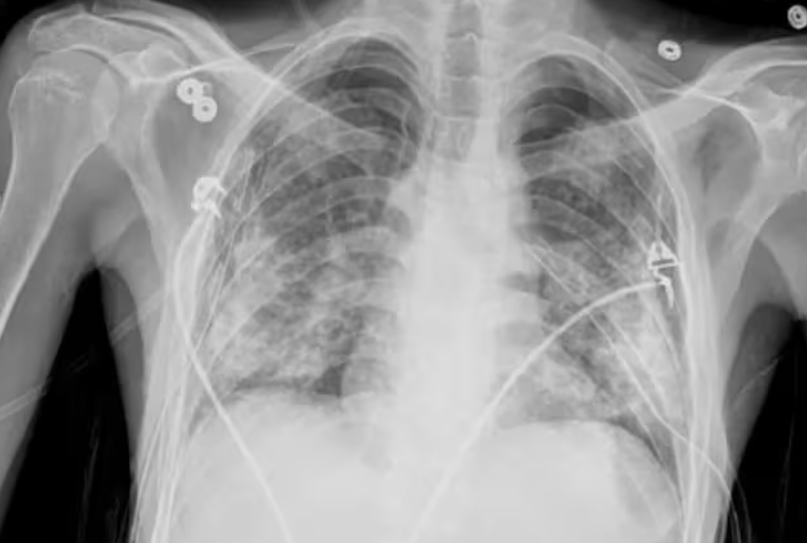

X-ray 사진 보는 법

X-ray 사진은 기본 원리를 알면 꽤 흥미로워요. 뼈처럼 단단한 조직은 방사선을 거의 통과하지 않아 흰색으로 보이고, 근육이나 지방 같은 조직은 회색, 공기처럼 비어 있는 공간은 검정색으로 나옵니다. 그래서 폐는 검게, 갈비뼈는 하얗게 보이는 거죠. 물론 정밀한 판독은 전문가에게 맡겨야 하지만, 기본적인 구조만 알아도 진료를 이해하는 데 큰 도움이 돼요.